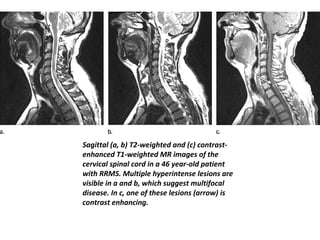

Sagittal (a, b) T2-weighted and (c) contrast-

enhanced T1-weighted MR images of the

cervical spinal cord in a 46 year-old patient

with RRMS. Multiple hyperintense lesions are

visible in a and b, which suggest multifocal

disease. In c, one of these lesions (arrow) is

contrast enhancing.

4 Sagittal (a, b)T2-weighted and (c) contrast- enhanced T1-weighted MR images of the cervical spinal cord in a 46 year-old patient with RRMS. Multiple hyperintense lesions are visible in a and b, which suggest multifocal disease. In c, one of these lesions (arrow) is contrast enhancing.